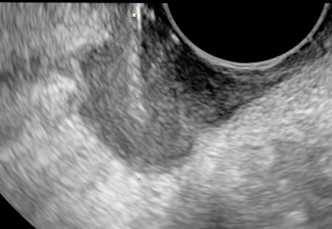

L’ecografia riveste un ruolo fondamentale nell’ inquadramento dei casi di sospetto impianto dell’embrione in sedi diverse dalla cavità uterina (GEU).

E’ spesso il metodo più attendibile per la diagnosi di gravidanza extrauterina, diagnosi che può avvenire in maniera diretta qualora venga chiaramente visualizzato l’impianto a livello delle tube (localizzazione più frequente) o di altre sedi, oppure indirettamente quando non si rilevi nulla a livello uterino nonostante valori delle beta HCG elevati e che tuttavia non aumentano come atteso.